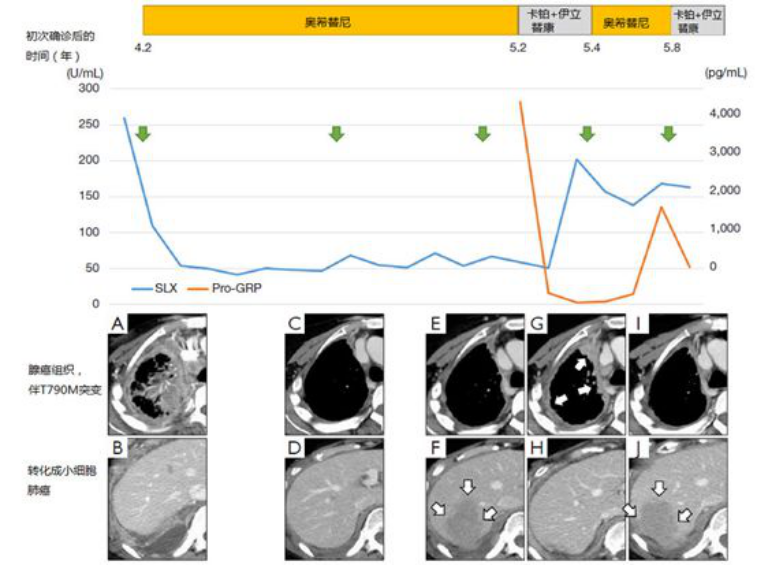

这里列举一例奥希替尼轮换治疗。一女性患者,61岁,晚期肺腺癌伴脑转,L858R阳性,先后使用吉非替尼、厄洛替尼、化疗,阿法替尼治疗了4.2年。患者的右胸膜转移灶测得T790M突变(组织为腺癌),但发现右横膈膜附近的胸膜肿瘤转化成小细胞肺癌。患者使用奥希替尼及化疗(卡铂+伊立替康)轮换治疗,在一处病灶发生进展后立即切换另一方案,具体见下图。